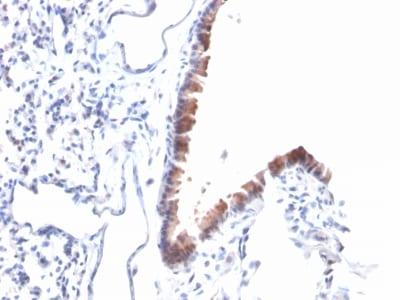

Mesothelin is a 40 kDa glycosyl-phosphatidylinositol-anchored glycoprotein cleaved from a 69 kDa precursor protein. Mesothelin immunoreactivity is high in cancers of the ovary (serous papillary, endometrioid and undifferentiated) and pancreas, with less frequent staining seen in adenocarcinomas of the endometrium, lung and stomach/esophagus. Mesothelin is one of the most sensitive markers for mesothelioma.Primary antibodies are available purified, or with a selection of fluorescent CF® Dyes and other labels. CF® Dyes offer exceptional brightness and photostability. Note: Conjugates of blue fluorescent dyes like CF®405S and CF®405M are not recommended for detecting low abundance targets, because blue dyes have lower fluorescence and can give higher non-specific background than other dye colors.

Positive Control

CAPAN-2 or HeLa cells. Lung Mesothelioma.

Mesothelioma|Ovarian cancer|Pancreatic cancer

IHC (FFPE) (verified)

Higher concentration may be required for direct detection using primary antibody conjugates than for indirect detection with secondary antibody|Immunohistology (formalin): 1-2 ug/mL for 30 minutes at RT|Staining of formalin-fixed tissues requires boiling tissue sections in 10 mM citrate buffer, pH 6.0, for 10-20 minutes followed by cooling at RT for 20 minutes|Optimal dilution for a specific application should be determined by user